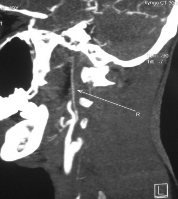

Hình 3.2b. Minh họa tắc động mạch cảnh trong hai bên - hai ca còn lại: TVG 74 tuổi (trái) và VHK 48 tuổi (giữa và phải), có tổn thương nhỏ vùng ranh giới, tắc động mạch cảnh trong hai bên với bàng hệ Willis từ hệ đốt sống thân nền qua động mạch thông sau.

Có 3 bệnh nhân (2,5%) tắc hoàn toàn động mạch cảnh trong đối bên, nghĩa là tắc động mạch cảnh trong cả hai bên (Hình 3.2 a,b). Ba mươi bệnh nhân (24,8%) có động mạch cảnh trong đối bên hoàn toàn bình thường. Còn lại đại đa số bệnh nhân có xơ vữa hẹp một phần động mạch cảnh trong đối bên (n=88; 72,7%, trong đó 7,4% hẹp nặng, 65,3% hẹp nhẹ).